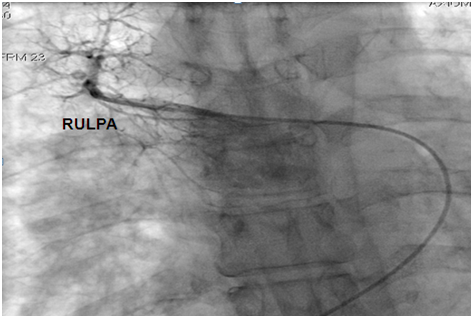

Figure 4: Hypotrophic RULPA without any veinous drainage. RULPA: Right Upper Lobar Pulmonary Artery.

Figure 5: Hypotrophic LULPA with no veinous drainage. LULPA: Left Upper Lobar Pulmonary Artery.